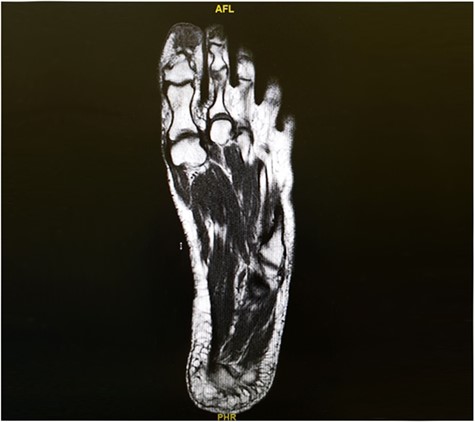

The patient was then referred to the infectious disease team, and a 6-week course of clindamycin was started to eradicate the infection. Follow up after 19 months shows no recurrence (Figs 4 and 5).

19 months post excision and coverage with Kutler bilateral V-Y advancement flaps with no evidence of recurrence.

Left foot X-ray 19 months post excision and coverage with Kutler bilateral V-Y advancement flaps no evidence of recurrence.